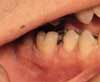

Figure 1

Herpes simplex. The 2 most common infectious conditions in the general practice setting are herpes simplex virus (HSV) infection (type 1 and, less frequently, type 2) (Figure 1) and fungal disease. These conditions are not generally mistaken for each other because their clinical presentations are quite distinct.HSV infection is sometimes confused with aphthous stomatitis (a noninfectious, immunologic-mediated condition precipitated by stress, food sensitivities, trauma, and endocrine disorders) because both of these conditions are characterized by multiple oral ulcerations. However, patients with primary HSV infection--unlike those with aphthous stomatitis (Figure 2)--present with extraoral symptoms including irritability, malaise, headache, and low-grade fever. Further, multiple pinhead lesions are observed on the attached gingiva surrounding the teeth and on the palate, 2 areas not affected in aphthous stomatitis. Both conditions are painful, but pain is generally more severe in patients with herpes simplex. Patients may not be adequately hydrated because drinking is painful. Examination reveals distinct halitosis and submandibular lymphadenitis.1 Both HSV infection and aphthous stomatitis are self-limited, but HSV infection has been associated with morbidity and, in rare cases, mortality.2